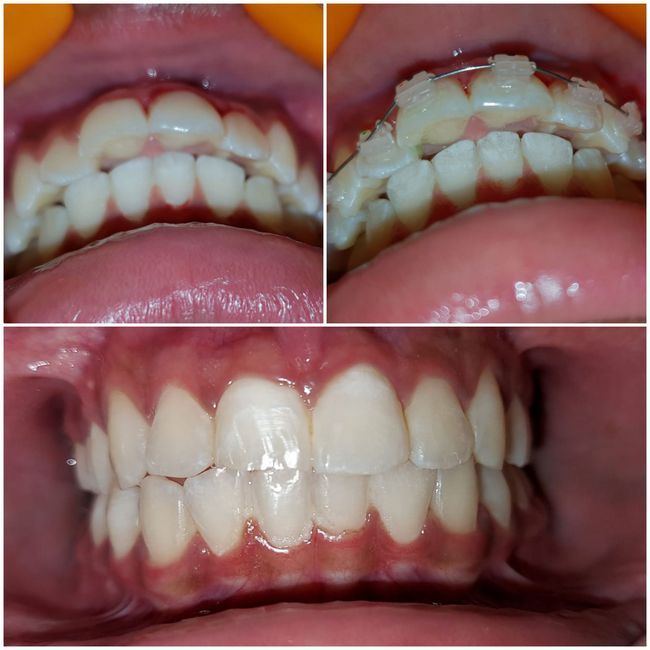

Case No: 11

Malocclusion Type: Class I Malocclusion with Crowding in upper and lower anteriors.